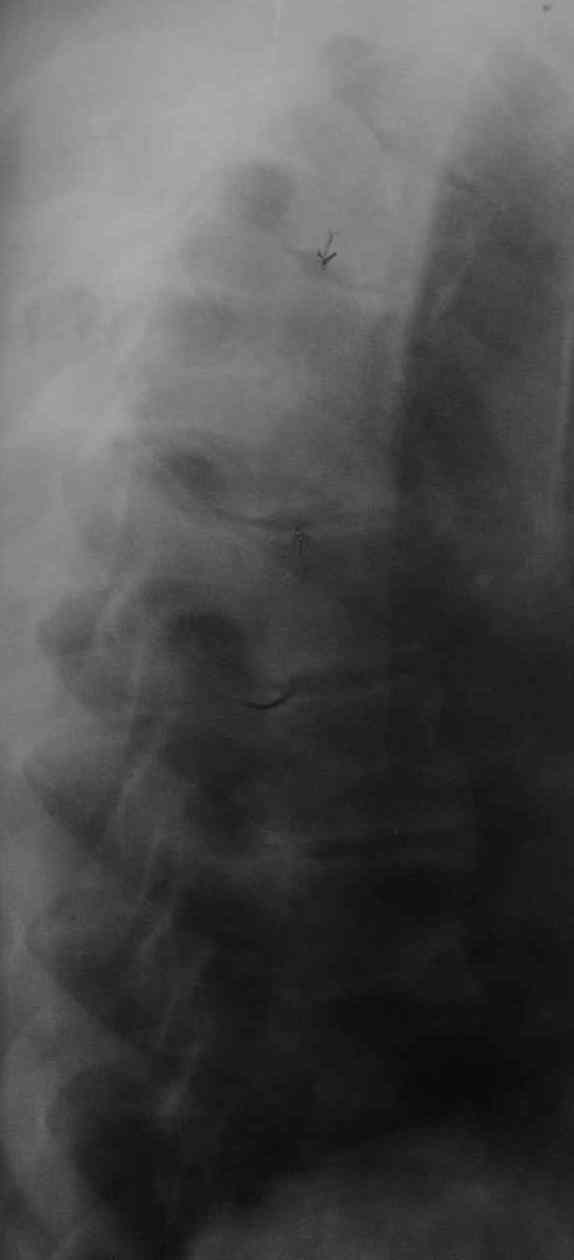

1. Rо-графия грудного и поясничного отделов позвоночника - деструкция с клиновидной деформацией Th5-6. Закл.: застарелый компрессионный перелом? Мт? 2. УЗИ внутренних органов - внутренние органы без патологии. Простата визуализируется с трудом. Края неровные, размеры 6,2х4,8х5,3 см., структура неоднородная. Объем мочевого пузыря - 600,0 мл. Заключение : Хр. б\к холецистит, Аденома простаты. Сч простаты? 3. ФГДС - заключение: Эрозивный дуоденит. Атрофический гастрит. 4. Рентгенография легких - без патологии. 5. Ретроспективный пересмотр флюорограмм за последние 3 года - без патологии. Повторно выполнены клинические и биохимические анализы крови. Заслуживает внимания только нарастание лейкоцитоза (L - 14,0П-4,С-68,Л-64,М-5, СОЭ - 65 мм.\ч). Ликвор: цвет - светло-желтый, ксантохромия- наблюдается, прозрачность - мутная, нейтрофилы - 95%, лимфоциты - 5%, цитоз - 588х106/л, белок - 9,9 промилей. В осадке - I пробирка: L- в большом количестве, Э- неизмененные, в большом количестве,Э- измененные, 1-3 в п\з. II пробирка: L - в небольшом к-ве, Э - неизмененные, 7-10 в п\з, Э- измененные, 2-3 в п\з. К ранее назначенному лечению добавлены инфузионная терапия, антибиотики ( цефтриаксон, ципринол), гормональная терапия (дексаметазон 8,0 мгх2 р\д), гепарин, диуретики, посиндромная терапия. Осмотрен урологом, онкологом. Достоверных данных за наличие Мт. не установлено. В связи с неясностью диагноза, был направлен на КТ в Тираспольскую РКБ. 21 марта больной скончался. На вскрытии - внутренние органы без признаков какой-либо патологии. При разведении волокон передней продольной связки в проекции Th4-6 была вскрыта гнойная полость с наличием деструкции тел указанных позвонков, с прорывом гнойника в позвоночный канал. Дуги и отростки позвонков - без признаков поражения. Гной сливкообразной консистенции, зеленоватого цвета. Гнойных затеков в мягких тканях также не обнаружено.Таким образом, выставлен п\а диагноз: гнойный остеомиелит тел Th4-6 c прорывом в позвоночный канал.

Насчет лечения - вполне адекватная консервативная терапия. Возможно было дополнить введение постоянного эпидурального катетера с введением антибиотиков и дренированием гноя(еще вариант - введение двух эпидуральных катетеров на разных уровнях, положение пациента на кровати с приподнятым головным концом, введение антибиотиков только в верхний. своеобразный "лаваж" позвоночного канала). Идеалом, конечно, была бы санация очага. На представленной КТ не совсем видно дату(сделана уже в период обострения?). На КТ можно заподозрить гнойную природу очага по плотности, характеру распространения. После удаления очага возможны множество вариантов выполнения дефектов.

Судя по представленным рентгенограммам и МР-томограмме (контактная деструкция тел позвонков, натечный абсцесс), анамнезу(медленное развитие заболевания) - нельзя было исключить туберкулезное поражение позвоночника. Собственно об этом забывать в таких случаях нигода нельзя. Так как тогда требуется специфическая противотуберкулезная медикаментозная подготовка.